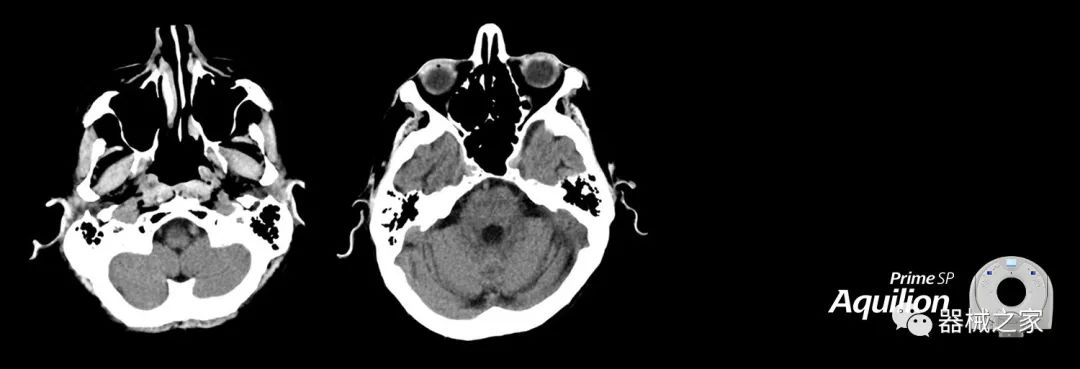

在以患者為中心的放射腫瘤學(xué)領(lǐng)域,計(jì)算機(jī)斷層掃描(CT)的可訪問性,可重復(fù)性和靈活性至關(guān)重要。為了建立這些價值,佳能醫(yī)療系統(tǒng)美國公司現(xiàn)在正在擴(kuò)大其放射腫瘤學(xué)CT模擬產(chǎn)品,包括Aquilion Prime SP和Aquilion Lightning 80高級CT系統(tǒng)。除了Aquilion LB之外,Aquilion Prime SP和Aquilion Lightning 80現(xiàn)在還包括放射治療(RT)選項(xiàng),可為腫瘤學(xué)規(guī)劃提供高質(zhì)量的CT成像和精密工具。

擴(kuò)展視野(EFOV)可以看到更多的解剖結(jié)構(gòu)。Aquilion LB采用85 cm EFOV,而Aquilion Prime SP和Aquilion Lightning 70采用70 cm EFOV。

Aquilion Prime SP使設(shè)施能夠處理具有挑戰(zhàn)性的案例,同時為員工提供快速,靈活和高效的解決方案。

兩個CT系統(tǒng)均采用0.5 mm x 80排PUREViSION探測器技術(shù)(可配置并從80-160現(xiàn)場升級),78 cm孔徑,50 cm視野,AIDR(自適應(yīng)迭代劑量減少)3-D和SEMAR(單個)能量金屬神器減少)技術(shù)。

Aquilion LB專為滿足腫瘤學(xué)挑戰(zhàn)而設(shè)計(jì),同時優(yōu)先考慮患者護(hù)理。Aquilion LB的內(nèi)徑為90 cm,能夠幫助復(fù)雜的患者設(shè)置并提高患者的舒適度。CT模擬定位可以輕松鏡像放射治療定位,更加自信。該系統(tǒng)采用0.5 mm x 16排(32層)PUREViSION探測器技術(shù),70 cm視野,AIDR 3D和SEMAR技術(shù)。